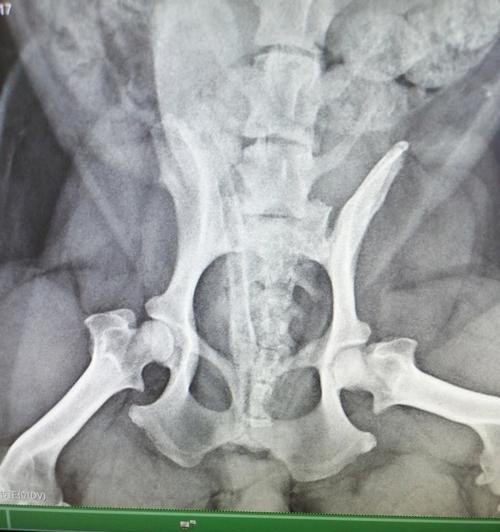

狗狗腿髋坏死:原因、预防与治疗全解析 腿髋坏死是影响狗狗健康的重要疾病,了解其成因和预防方法对保护宠物至关重要。通过合理饮食、运动和定期检查可有效降低患病风险。治疗方式包括非手术和手术,需根据病情选择。术后康复和心理支持同样关键,主人的耐心与关爱将帮助狗狗更好地恢复。 科学养宠知识 2026-02-17 05:20 浏览:692